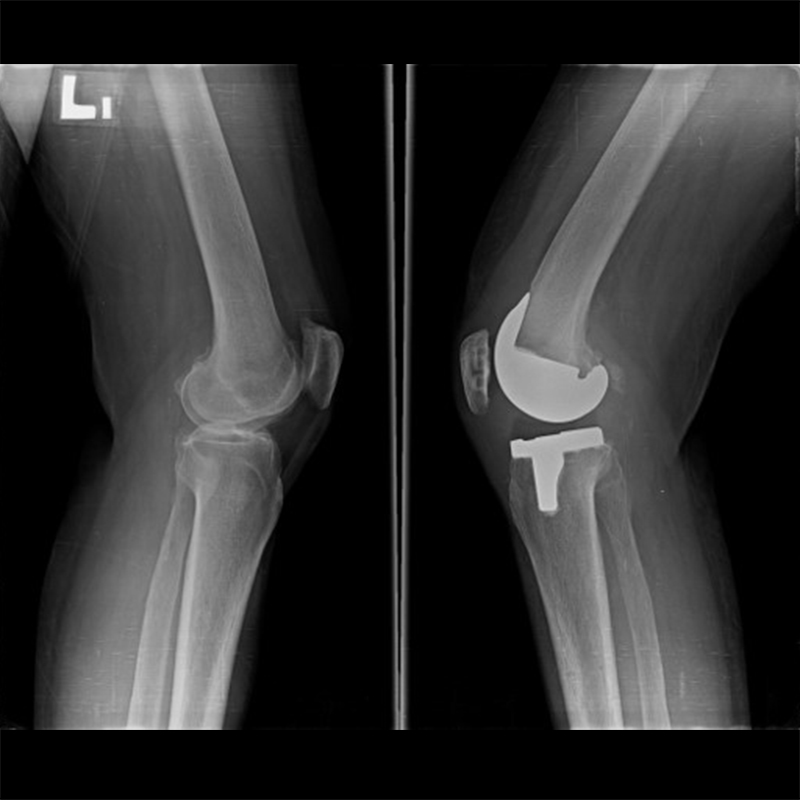

機器手臂手術 首頁 案例分享 膝關節手術 機器手臂手術 蔡女士 78歲 術前 術後 陳女士 70歲 術前 術後 術前 術後 ANGEVINE女士 73歲 術前 術後 U.S.A Mark 73歲 術前 術後 藍女士 78歲 術前 術後